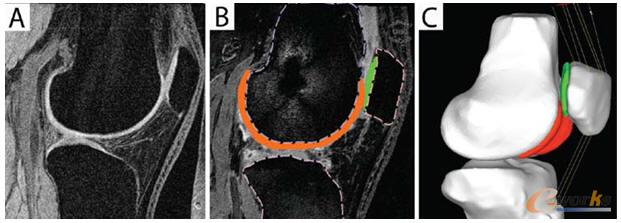

USC成像研究中心根據醫學成像標準對處于特定負重條件的研究對象的膝蓋進行核磁共振掃描,并將掃描結果以數字文件的形式發送給Farrokhi。每份文件都是患者膝蓋的二維數字圖像切片。Farrokhi使用Tomovision提供的Sliceomatic軟件工具在其中的120張切片上勾畫出感興趣的結構,然后將這些結構劃分為單個3D圖像。之后,他將3D圖像保存為.STL文件并將其導入HyperMesh。

“我們非常關注核磁共振圖像上的五個部分,”Farrokhi表示,“股骨、脛骨和髕骨;覆蓋在股骨上的軟骨以及覆蓋在髕骨上的軟骨。模型的總體輸出是這兩個軟骨表面之間所產生的應力。”

Farrokhi在HyperMesh中針對模型生成一個表面,然后將骨幾何創建為剛體薄殼網格。他還創建了多個四面體元來表示軟骨的厚度。完成建模后,他將模型發送到有限元求解器,以對膝蓋向下彎曲15、30和45度時兩個軟骨之間的應力進行仿真。